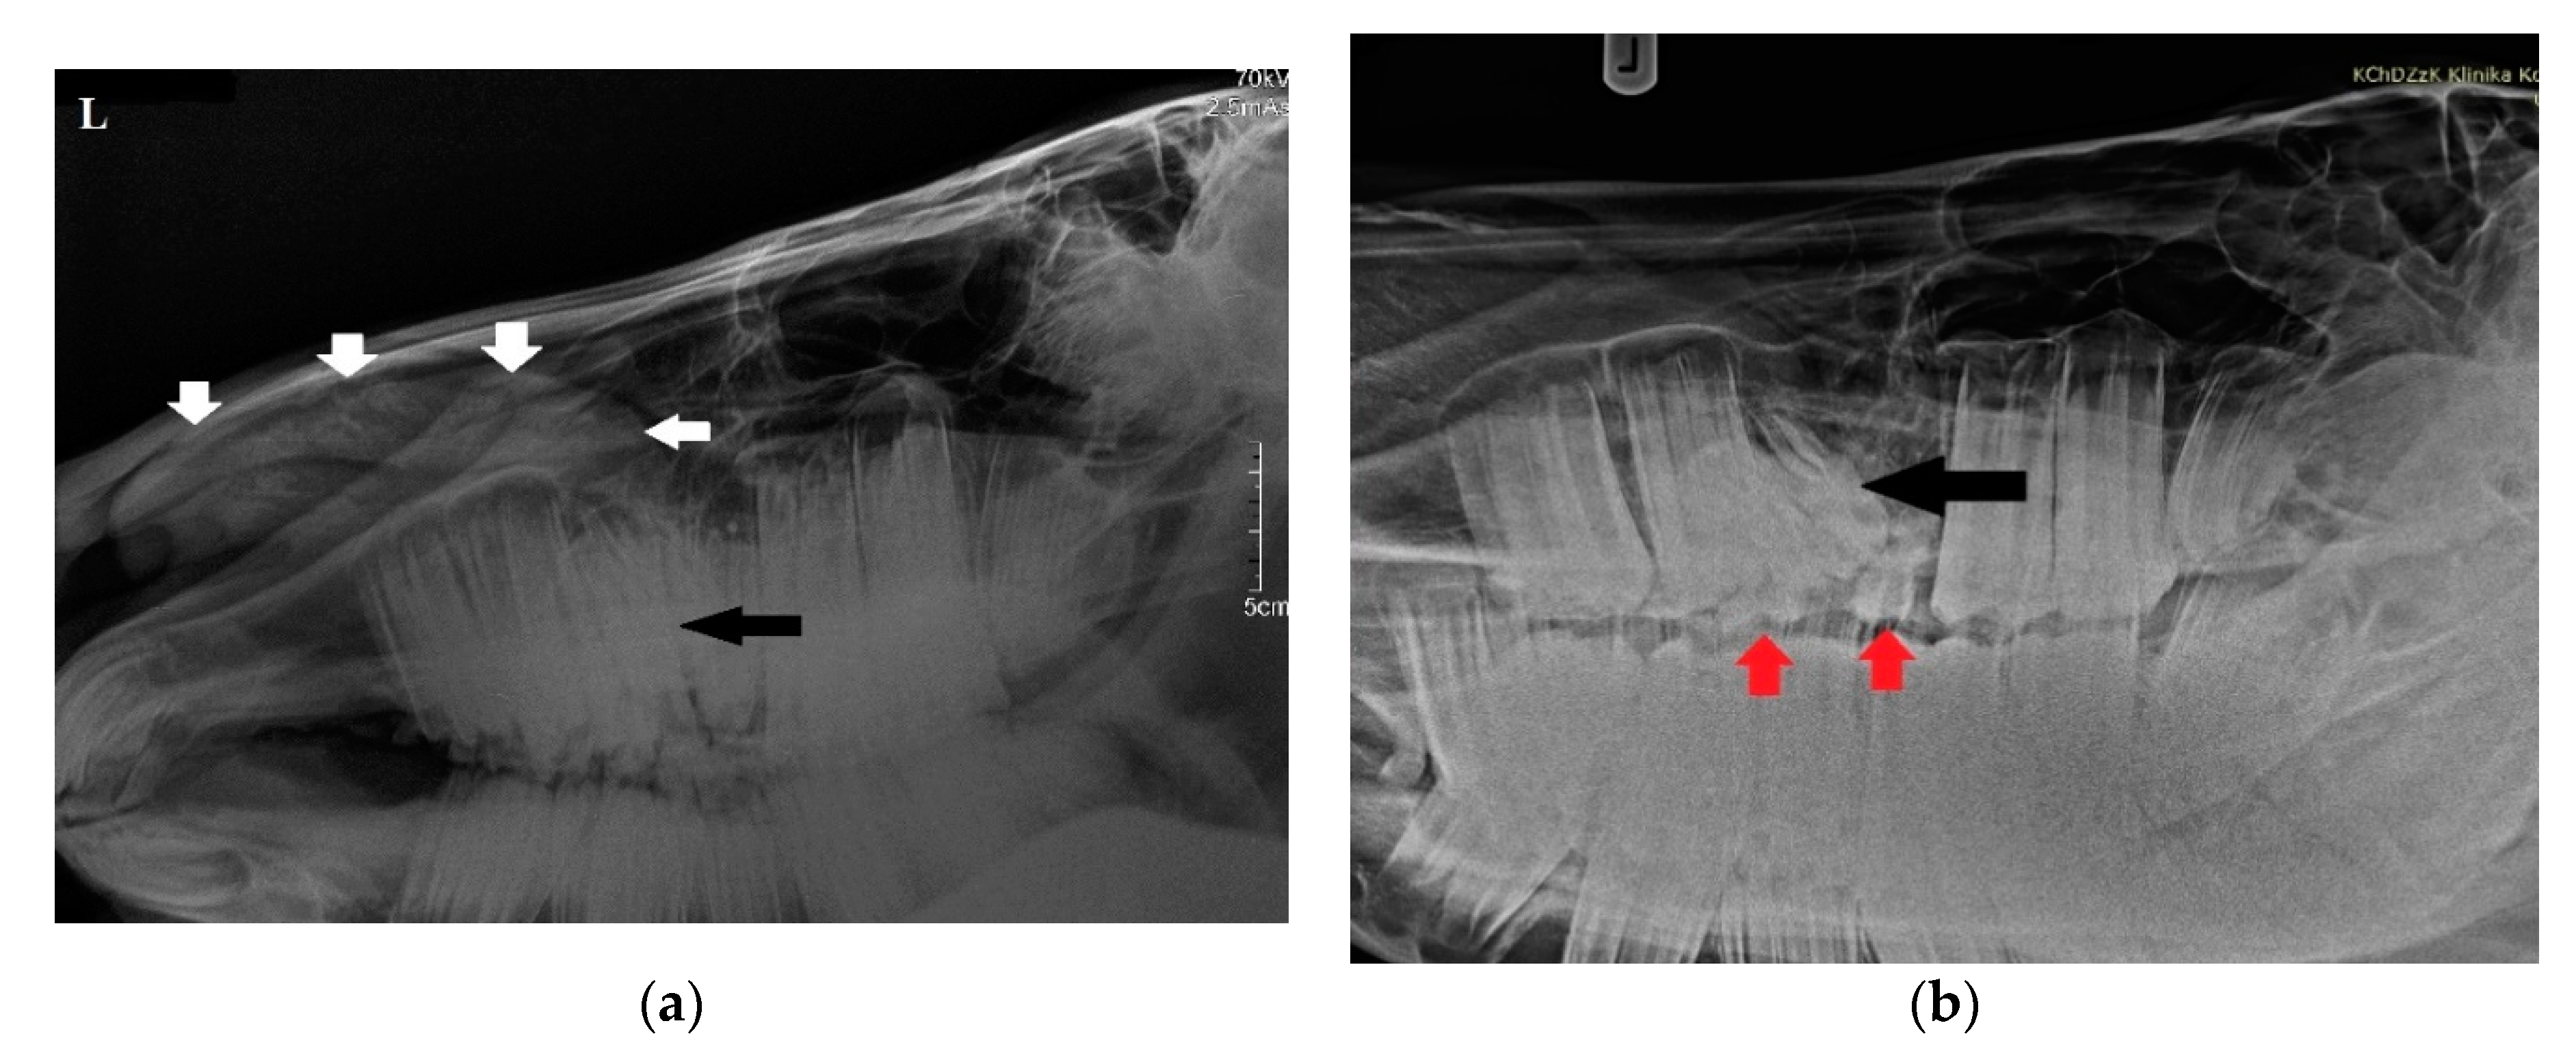

Radiographs were obtained by computed radiography (Gierth HF 80 Plus, Gierth X-ray International, Germany, and Console Advance DR-ID 300 CL, Fujifilm Corporation, Tokyo, Japan) with an indirect conversion system for scanning. The left latero-lateral (LL) and right 30° dorsal–left ventral oblique (Rt30D-LeVO) projections were assessed. A well-delineated, oval-shaped, and slightly heterogeneous mineral opacity was seen within the left nasal passage, extending from the level of 208 to the nostril (Figure 2a) []. Triadan 208 was displaced into the rostral aspect of the nasal cavity. The morphology of tooth 208 was abnormal, with markedly variable radiopacity and hypoplastic reserve, and clinical crown. Deciduous teeth 607 and 608 were visible (Figure 2b). The right and left maxillary sinuses remained intact.

Figure 2.

(a) Radiographic examination in latero-lateral projection demonstrating a well-demarcated mass within the nasal cavity (white arrows) and displaced Triadan 208 (black arrow). (b) Rt30D-LeVO projection of the maxillary region revealing hypoplastic dislocated maxillary last premolar (black arrow). Clearly visible deciduous Triadan 607 and 608 (red arrows).